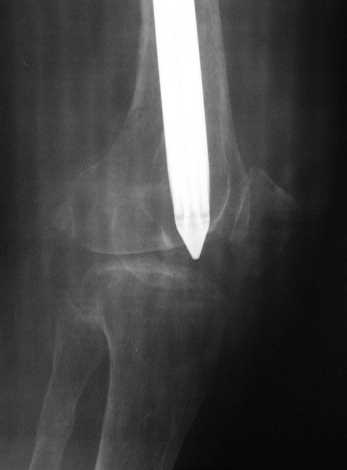

Анамнез: В 2005 году в ЦРБ - остеосинтез перелома бедра пластиной. В 2007 г. воспаление в ср. трети бедра и удаление пластины. Через 2 мес. - рефрактура и фиксация гвоздем "фикшн". Через 2 мес. после синтеза - свищ, "функционирующий" по настоящее время. Что делать?

Правда, что делать с отверстием в колено, вернее как провести санацию так чтобы минимизировать риск распространения инфекции в коленный сустав, представляется не очень четко.